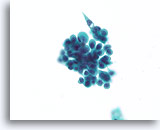

Papilloom, Borst FNA, Celblok.

Deze afbeelding van dezelfde FNA als in afbeelding 18 bevat een duidelijk papillaire architectuur.

Papilloom, Borst FNA, Celblok.

Deze afbeelding van dezelfde FNA als in afbeelding 18 bevat een duidelijk papillaire architectuur.